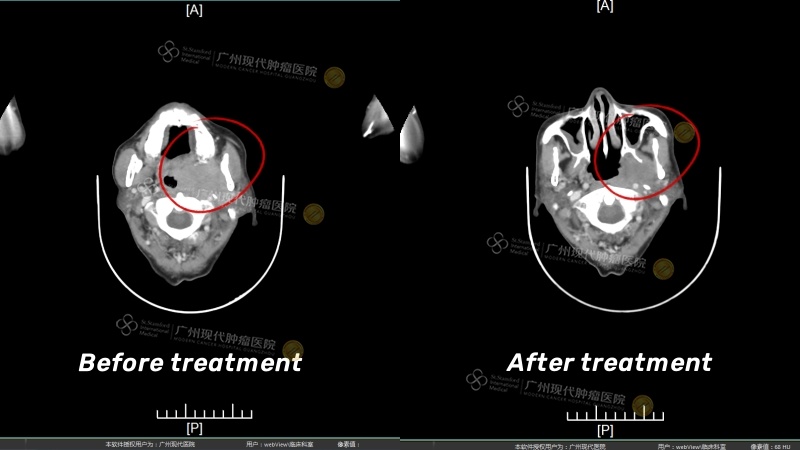

寻寻觅觅中,我找到了肿瘤专科医院——广州现代肿瘤医院,也了解医院的治疗技术特色是副作用极小、恢复快、并发症少的微创治疗,于是2023年11月,我便不远万里来到广州,找到了医院。MDT专家团队根据检查结果为我制定以微创介入治疗为主的治疗方案。微创介入治疗是把药物浓度比全身化疗药物高8-10倍,且不伤害正常细胞。通过特别小的管道以电脑影像的指示,把抗肿瘤药物灌注到肿瘤部位。

未经治疗前,我每天觉得嘴巴干渴,听力不稳定,鼻腔感到异常而且难吞咽,舌头麻木、口齿不清,还经常低烧,流鼻血。可经一次疗程后,在短短的几天里我身上的所有症状都明显消失:鼻血、低烧、舌头异常、鼻腔异常等症状都消失了!听力也正常了!经三次微创治疗后,不仅没有出现全身化疗所带来的痛苦,不会让我的身体承受不住晕倒,而且鸡蛋大小的肿瘤几乎消失了!

治疗前,肿瘤大小约6.1cmx4.0cm完全堵塞鼻咽

治疗后肿瘤明显缩小